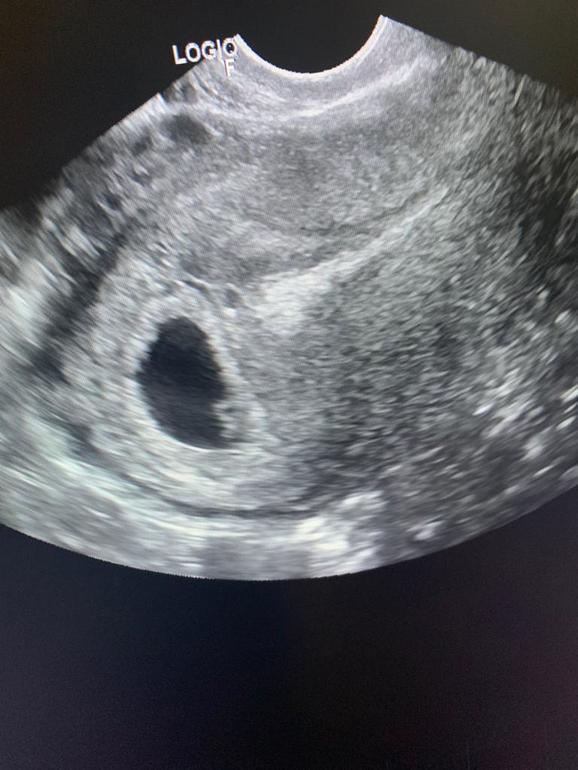

Сегодня нам 6 недель ровно. Вчера была на Узи, нашли малыша и сердечко послушали. Все на месте. Соответствуем сроку. А вот и мы:

Слава богу один))) а то ХГЧ настораживал. 18дпо был 1556, 22дпо 6851. Сегодня 30дпо, сдала ради интереса, вот жду ответ. У кого какие показатели были?

Пришли результаты ХГЧ 30дпо 28901. Калькулятор пишет мало. Переживаю теперь...(((

У меня с девочками хгч зашкаливало, на 22дпо было 14500 и 16200, это с 5 и 6. С 4 на 3 ден ь задержки было 1730. А узи в вас было вагинальное? Если да, то похоже на девочку😊

Да вагинальное. Но она не мерила ничего. Просто посмотрела что в матке и живой. Почему думаешь что девочка? Я как раз девочку хочу)))

По методу Рамзи, малыш сейчас справа сидит. Если было вагинальное, то девочка справа, мальчик слева. У меня сейчас слева сидит, тоже хочу, что бы сработал метод. Ну и хгч с девченками зашкаливает всегда